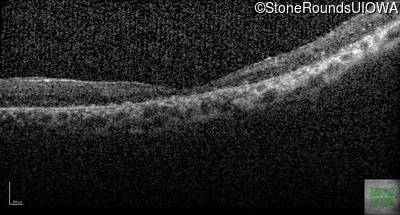

Age at visit: 41 years

OD OS